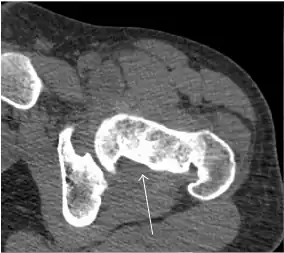

Synovial chondromatosis can be confidently diagnosed by X-ray when calcified cartilaginous chondromas are seen. However, other synovial proliferative processes, such as pigmented villonodular synovitis, require MRI for accurate diagnosis, although noncalcified synovitis can be suspected in radiographs by indirect signs, such as soft tissue swelling and/or erosions in the femoral head, femoral neck, or acetabulum (Figure 7).[1]

Figure 7:

-

Axial CT image of pigmented villonodular synovitis eroding the posterior cortex of the femoral neck.[1] -

Sagittal T2* gradient echo image showing a posterior soft tissue mass with hypointense areas secondary to hemosiderin deposition.[1] -

X-ray of synovial chondromatosis.[1] -

CT of synovial chondromatosis.[1]

In synovial proliferative disorders, MRI demonstrates synovial hypertrophy. In the case of PVNS, characteristic foci of low signal intensity related to hemosiderin deposition are better seen on gradient echo T2* images (Figure 7). In the case of synovial osteochondromatosis, the synovial hypertrophy is accompanied by intermediate signal cartilaginous loose bodies and/or low signal calcified loose bodies.[1]

Computed Tomography

Due to radiation concerns, CT has been relegated after MRI in the study of intra-articular causes of hip pain. The only exception where CT is considered superior to MRI is in bone tumors, because of its ability in characterizing matrix calcifications, and in depicting the anatomy of acute traumatic fractures. Typical matrix calcifications include the following: (a) osteoid mineralization, like a dense cloud, (b) chondroid calcification, reproducing a punctate popcorn pattern, or (c) fibrous calcification, ground glass-like appearance. There are also tumors that typically do not show matrix calcification. CT is also used for accurate localization of the nidus in osteoid osteomas and this must be differentiated from Brodie’s abscess or a stress fracture. The current standard treatment of osteoid osteoma is percutaneous radiofrequency ablation and this is usually performed under CT guidance.[1]